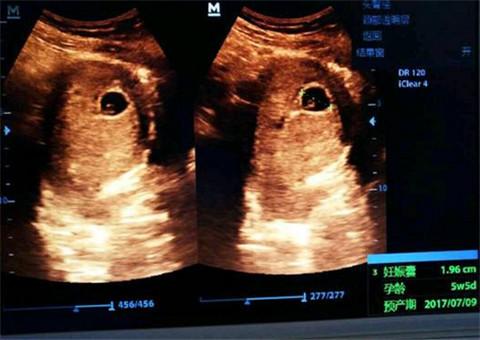

家里有人怀孕了全家都开心激动地不得了,家里要添新成员了是件大喜事。可是天有不测风云,孕期妈妈们要是出了一点点小问题全家人都跟着着急上火。很多妈妈辛辛苦苦怀上孩子却因为种种原因终止妊娠,孕妇怀孕2月还没胎心,只能放弃,找医生要来解释后哭背气。

没有胎心是很多准妈妈遇到过的情况,是自然流产,妈妈们往往会很难过,但是有些过来人 的经历告诉我们,即使检查了没有胎心,也要多检查几遍,不要立马放弃,有一个妈妈在三家医院检查都说没有胎心,最后去检查的时候医生说孩子胎心正常了,妈妈喜极而泣。

妈妈们怀孕时或多或少会出一点问题,妈妈们要做好孕期检查,无胎心时也不要着急,积极配合医生治疗,原因多种多样,搞清楚原因后再对症下药。